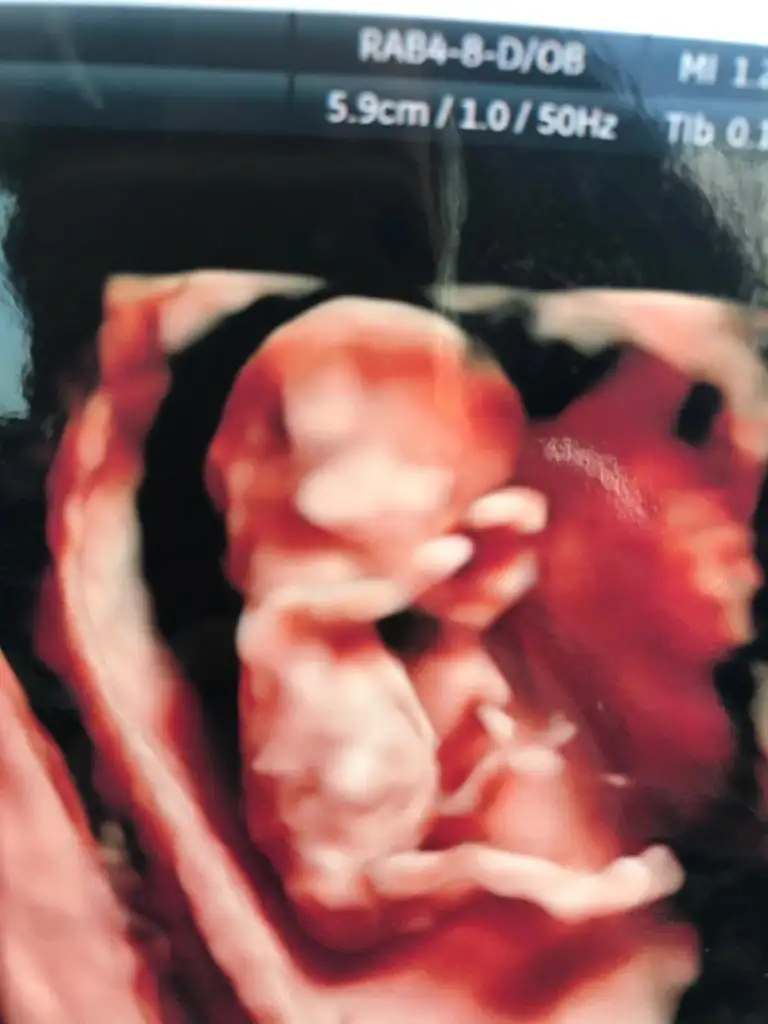

Bnm bebişe mi dedinErkek bu görmüyor musunuz kocaman şeyini

Yok cnm cinsiyet için hiç bişey söylemediKız canım zaten nub olmaz 13+4 haftada ya pıtış ya pipi olur bu bebek bence kız dr tahmin etmedini

Erkek gibi geldi banaCocoChanelmademoiselle Ikra meyra M mely15 sizlerin yorumunu merak ediyorum bugün ki ultrason görüntüleri

Kız diyorumCocoChanelmademoiselle Ikra meyra M mely15